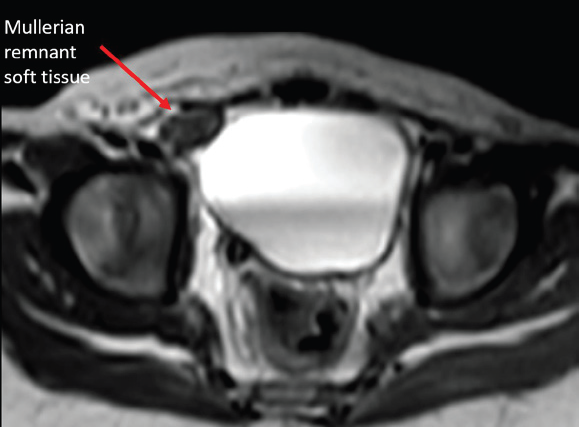

MRI pelvis was performed for soft tissue characterization. T2- weighted sequences demonstrated two testes on the right side—one within the scrotum and the other at the superficial inguinal ring. The ectopic left testis was smaller than the right testis. Additionally, an intermediate-signal-intensity structure was noted in the right inguinal canal, distinct from both testes, suggestive of a Müllerian derivative [Figure 4-6].

Figure 4: Coronal T2-weighted MRI showing bilateral testes located on the

same side of the pelvis—one in the scrotum and the other in the inguinal ring.

Figure 5: Oblique sagittal T2-weighted MRI demonstrating a soft tissue

structure in the superficial inguinal ring, different in signal intensity from the

testes, suspicious for Müllerian remnant.